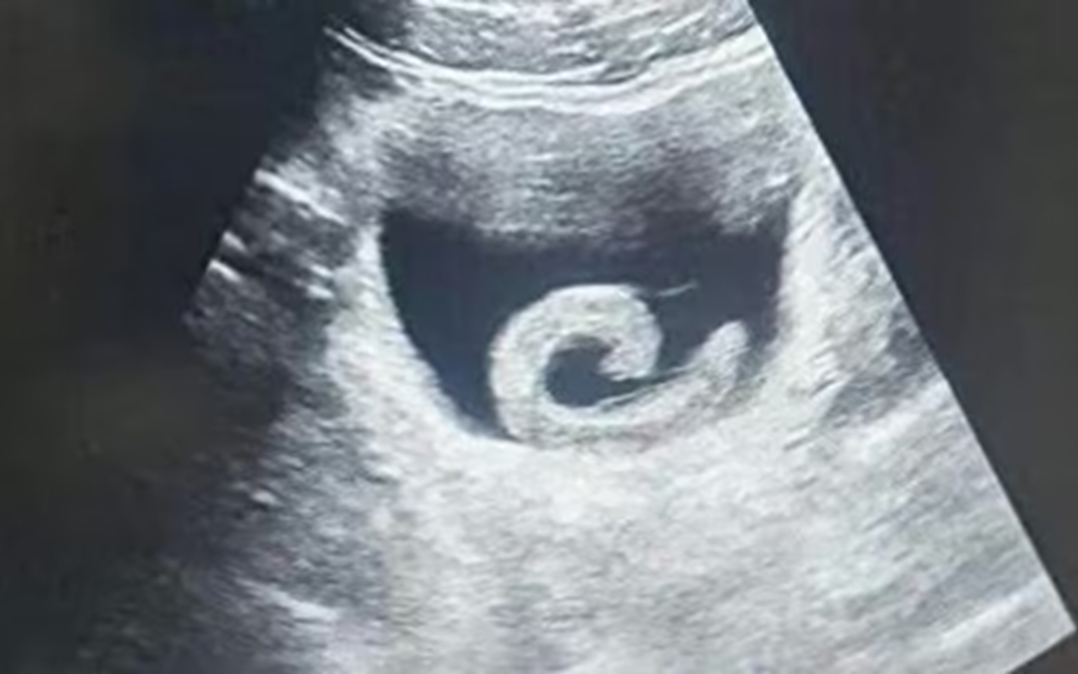

Kết quả chụp chụp MRI cho thấy cụ B.Ph. có một khối u nhầy xoang bướm. Ảnh: Báo Thanh Niên.

Kết quả MRI cho thấy không ghi nhận xuất huyết, nhồi máu hay khối u não mà xác định bệnh nhân bị u nhầy xoang bướm gây lan vào đỉnh hốc mắt trái.